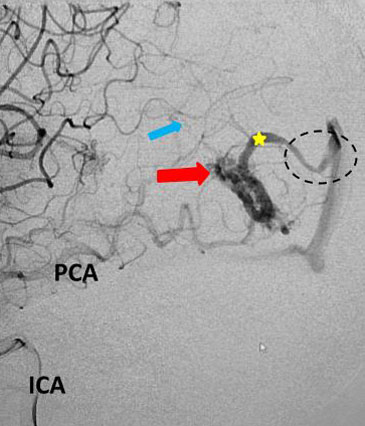

Fig 1. Head CT scan showing large right-sided, parieto-occipital intra-cerebral hemorrhage (ICH) and small occipital and temporal subdural hemorrhage (SDH) with right to left midline shift (red arrow).

A head CT revealed a large posterior-parietal intracerebral bleed, an acute subdural clot, and right to left midline shift (Fig 1). Following the review of a head CTA, the patient was diagnosed with a ruptured brain arteriovenous malformation (AVM). Urgent treatment was indicated for this acute intracerebral hemorrhage (ICH) with significant mass effect and the risk of catastrophic rebleeding of the AVM.